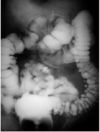

PRESENÇA DE LESÃO À NÍVEL DE COLON TRANSVERSO. POIS O CONSTRASTE NÃO PASSA NO NÍVEL DO CÓLON TRANSVERSO . JÁ NO CÓLON ESQUERDO VOCÊ NOTA A PRESENÇA DO CONTRASTE.